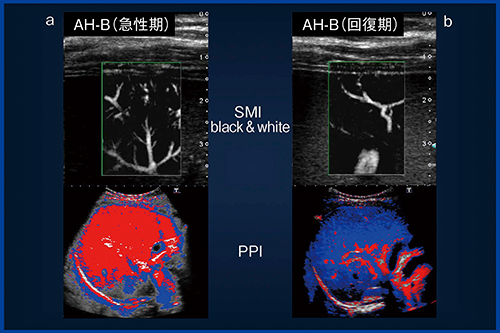

急性肝炎では,SMIで細かい血管が観察される急性期(図9a)には,造影超音波(PPI)では赤が広範囲に広がり動脈化が認められた。一方,SMIで動脈がほとんど観察されない回復期(図9b)には,造影超音波(PPI)も青が主体となり,門脈由来の灌流に回復していることが確認できた。

また,慢性肝炎と肝硬変を比べると,SMIで動脈が多く確認される肝硬変(図10b)では,造影超音波(PPI)でも動脈化が確認できるのに対し,動脈がほとんど見られない慢性肝炎(図10a)では,血流バランスが門脈に傾いていることがわかる。

図9 動脈が見える症例と見えない症例の比較:急性肝炎

図10 動脈が見える症例と見えない症例の比較:慢性肝炎と肝硬変